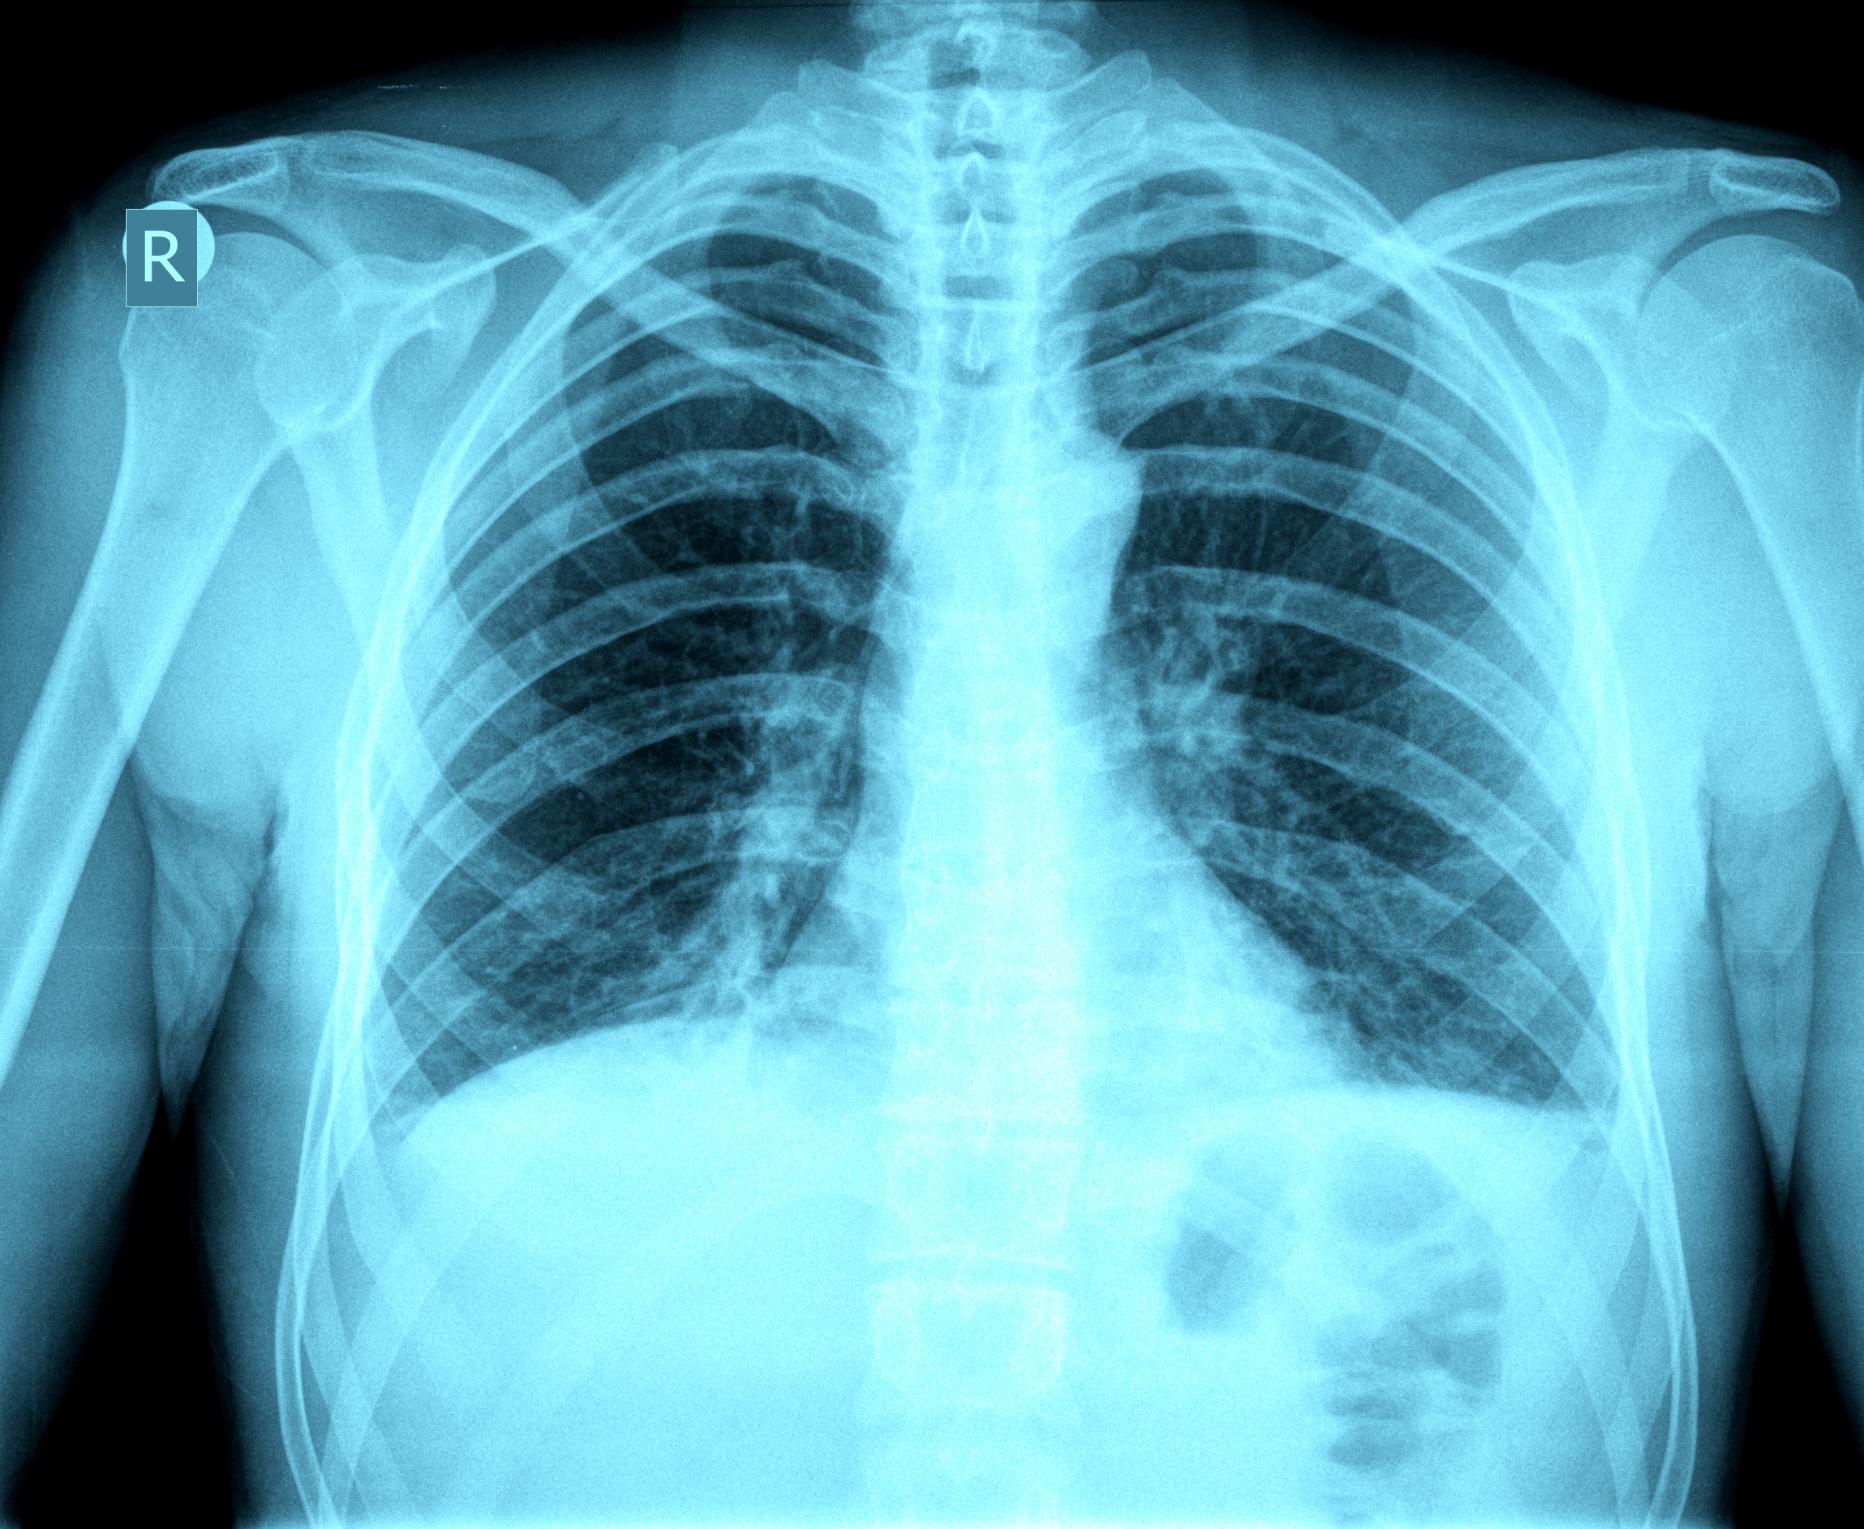

© Getty Images/iStockphoto / oceandigital/iStockphoto

Studie: Neuartiges Tuberkulose-Medikament heilt 9 von 10 Patienten

Mehr als 90 Prozent der mit multiresistenten Tuberkulose-Erregern infizirten Patienten könnten geheilt werden.